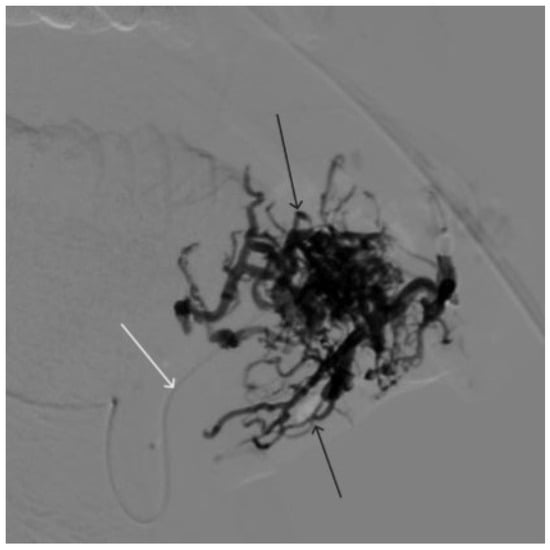

A 58-year-old male patient was admitted to the clinic complaining of a palpable formation in the left submandibular region. When angiography was performed, the filling of the vascular network of the tumor of the left submandibular region from the branches of the left occipital artery, as well as the muscular branches of the left vertebral artery, was noted (Figure 11). The patient underwent intravascular embolization of the paraganglioma with 7.5 mL of non-adhesive composition ONYX18 (Figure 12 and Figure 13). The vascular network supplying the paraganglioma was partially switched off (Figure 14). There were no complications. The mRs score at discharge was 1.

Figure 14. Digital subtraction angiography from the left common carotid artery: (a) direct projection, (b) lateral projection (white arrows indicate the guiding catheter in the left external carotid artery, black arrows indicate the boundaries of the embolized paraganglioma).